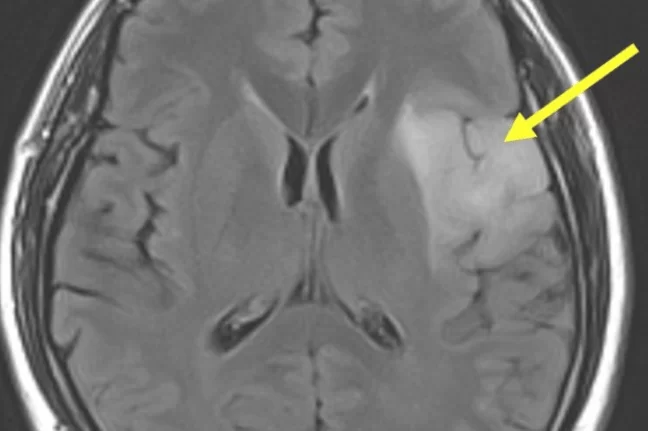

Μηνιγγίωμα: Τύποι, Συμπτώματα, Διάγνωση, Θεραπεία, Κίνδυνος Κακοήθειας και Νέες Εξελίξεις 2026

Αυτό το άρθρο προσφέρει μια ολοκληρωμένη επισκόπηση για τα μηνιγγιώματα, του πιο κοινού πρωτοπαθούς όγκου εγκεφάλου στους ενήλικες. Εξερευνά βασικές πτυχές όπως την προέλευση του …